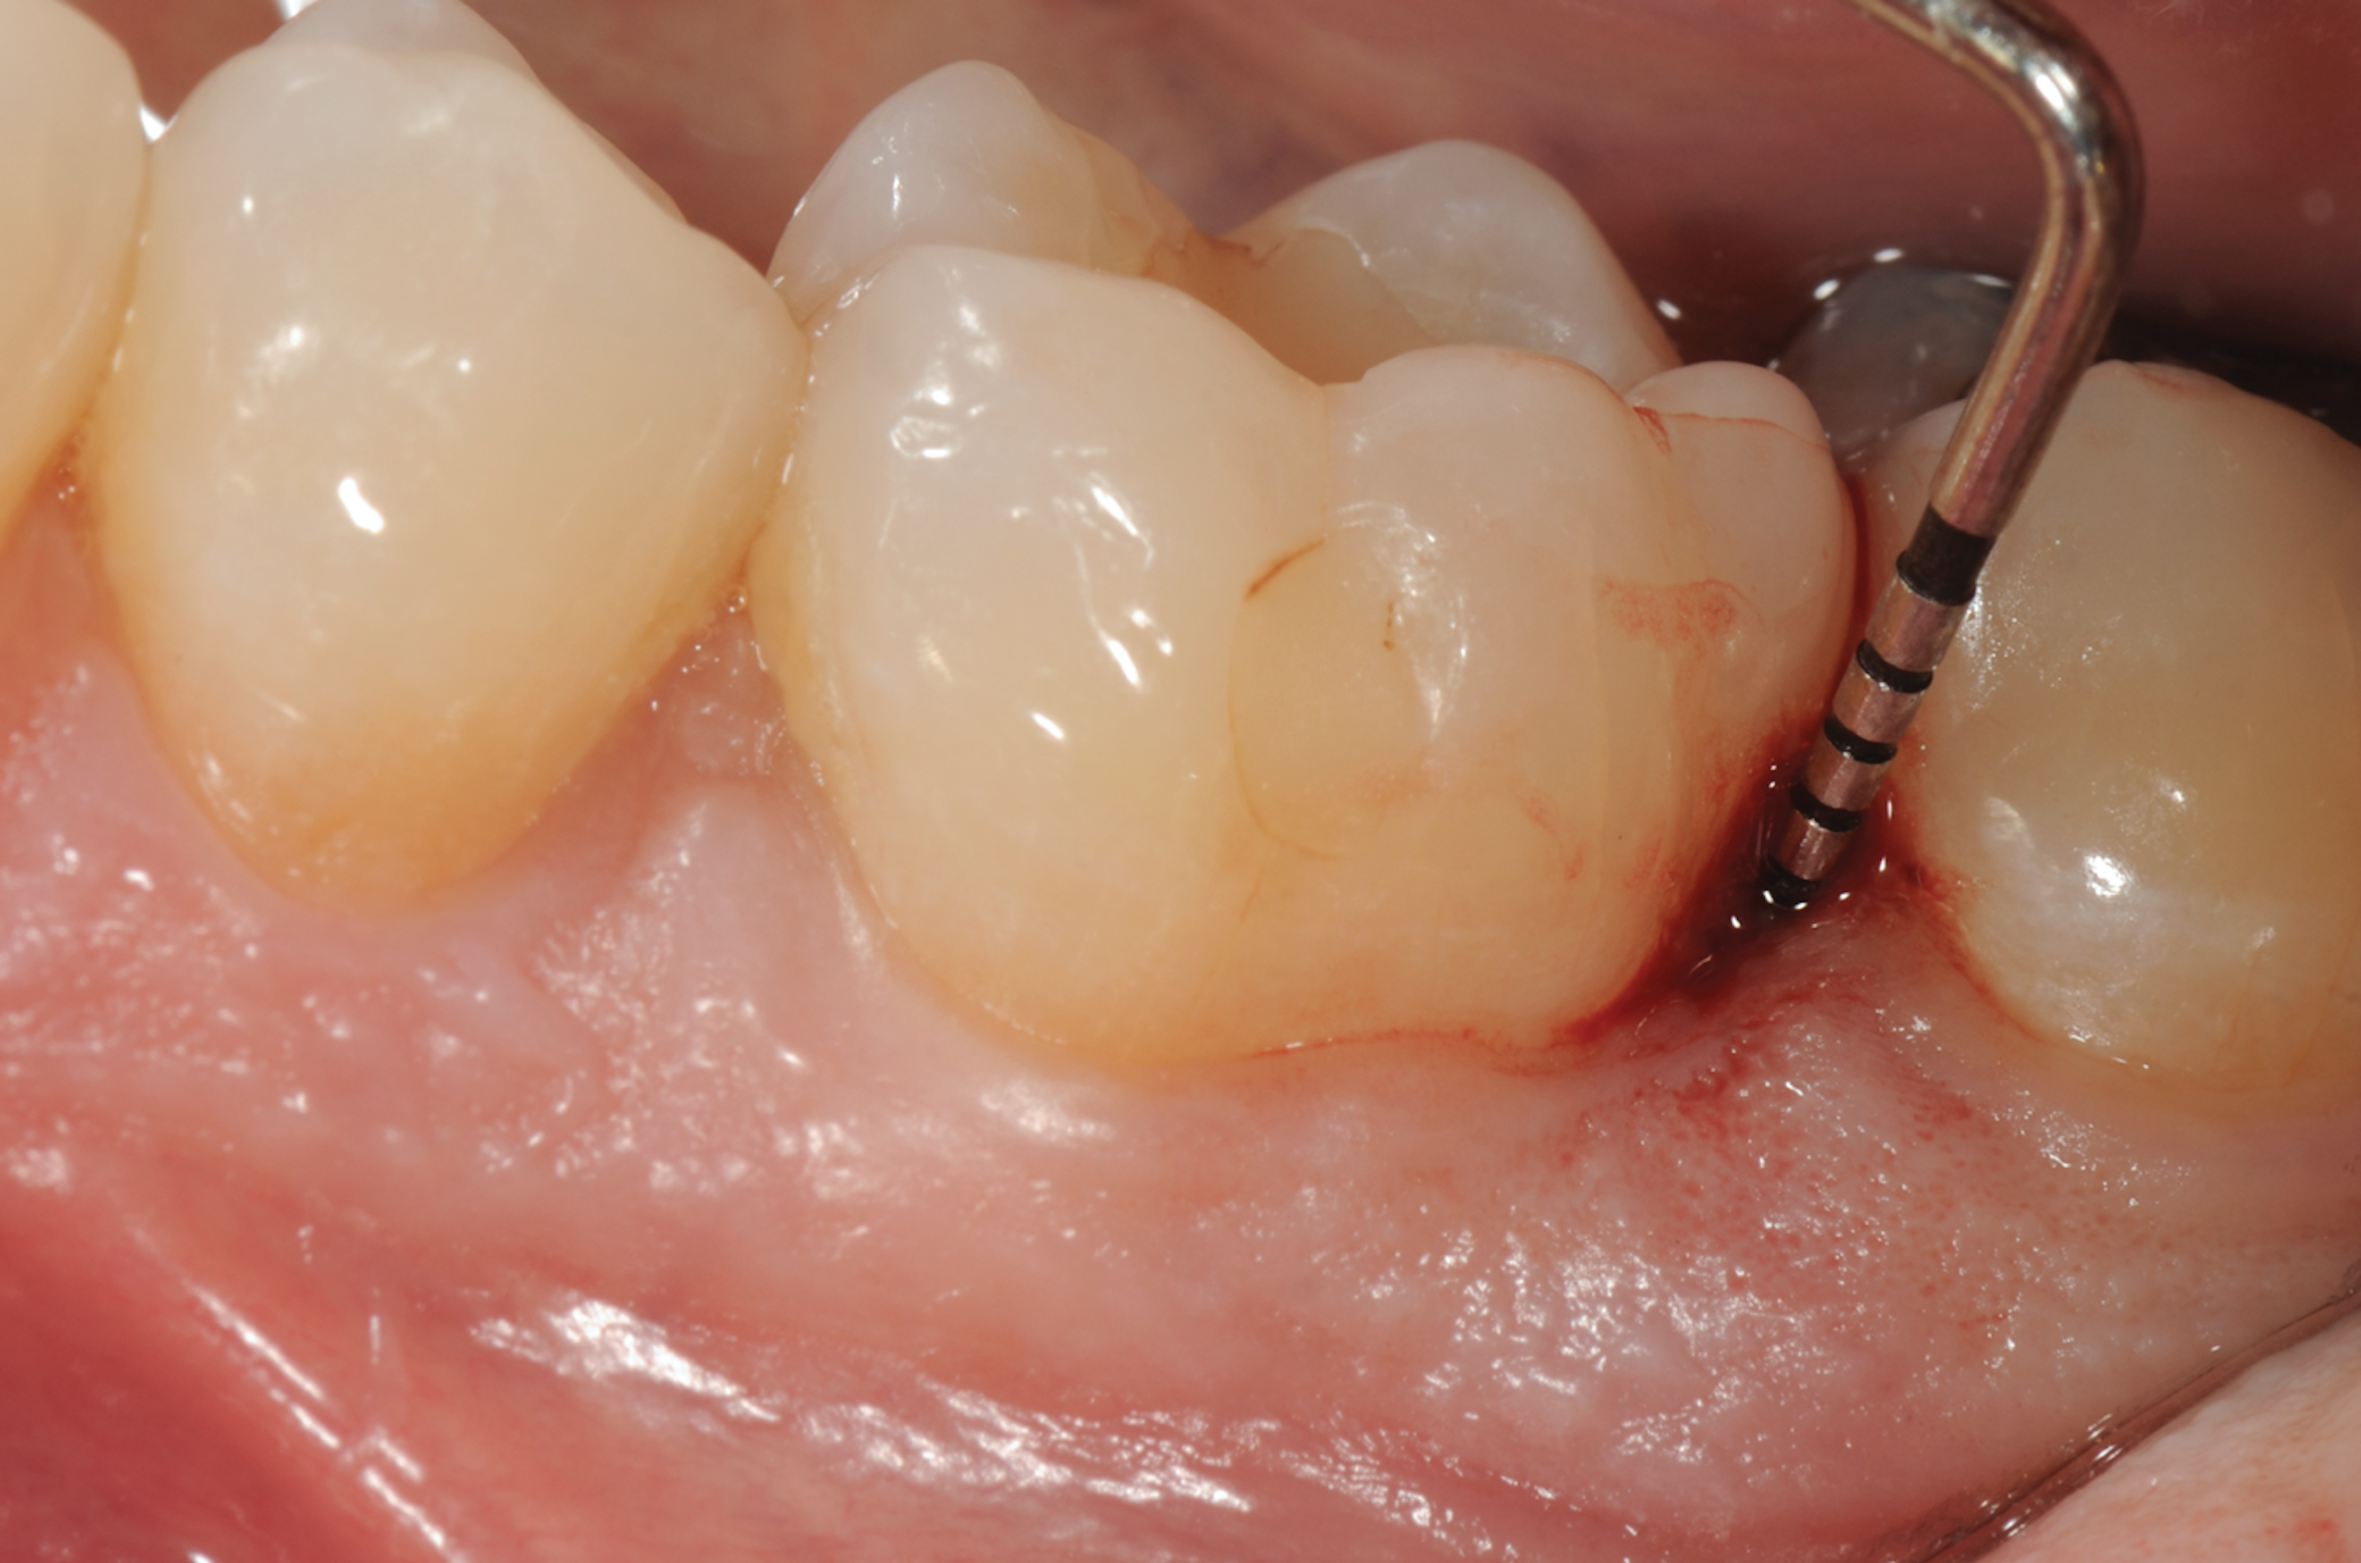

Fig 3. Distal probing depth of 10 mm at tooth No. 19.

Figure 3

In the case presented, a 56-year-old healthy nonsmoking male patient, diagnosed with periodontitis stage III, localized, grade B, had been under care in a private practice periodontal office (RAL) for 25 years. He had a history of good compliance with his treatment (full-mouth plaque score <20%). During the COVID-19 pandemic, the patient missed three supportive periodontal therapy (SPT) visits over a year, resulting in periodontal breakdown interproximal between teeth Nos. 18 and 19 (mandibular left second and first molars, respectively). At his most recent periodontal maintenance visit, significantly increased periodontal probing depths of up to 10 mm with bleeding on probing were noted (Figure 1 through Figure 3). The periapical radiograph revealed a deep, narrow three-wall intrabony defect at the distal aspect of tooth No. 19, with class I buccal furcation involvement (Figure 4). According to the periodontal risk score (PRS),15 formerly known as the Miller-McEntire periodontal prognosis index, the tooth prognosis at the patient's initial examination was "good" (score = 5), taking into account that he was unaware of his hemoglobin A1C (HbA1c) levels. This scoring motivated the patient to be tested, and his follow-up HbA1c was <6%, thus reducing his PRS to 3, which was considered "excellent," as the PRS target goal for regenerative procedures is a score of <5.15